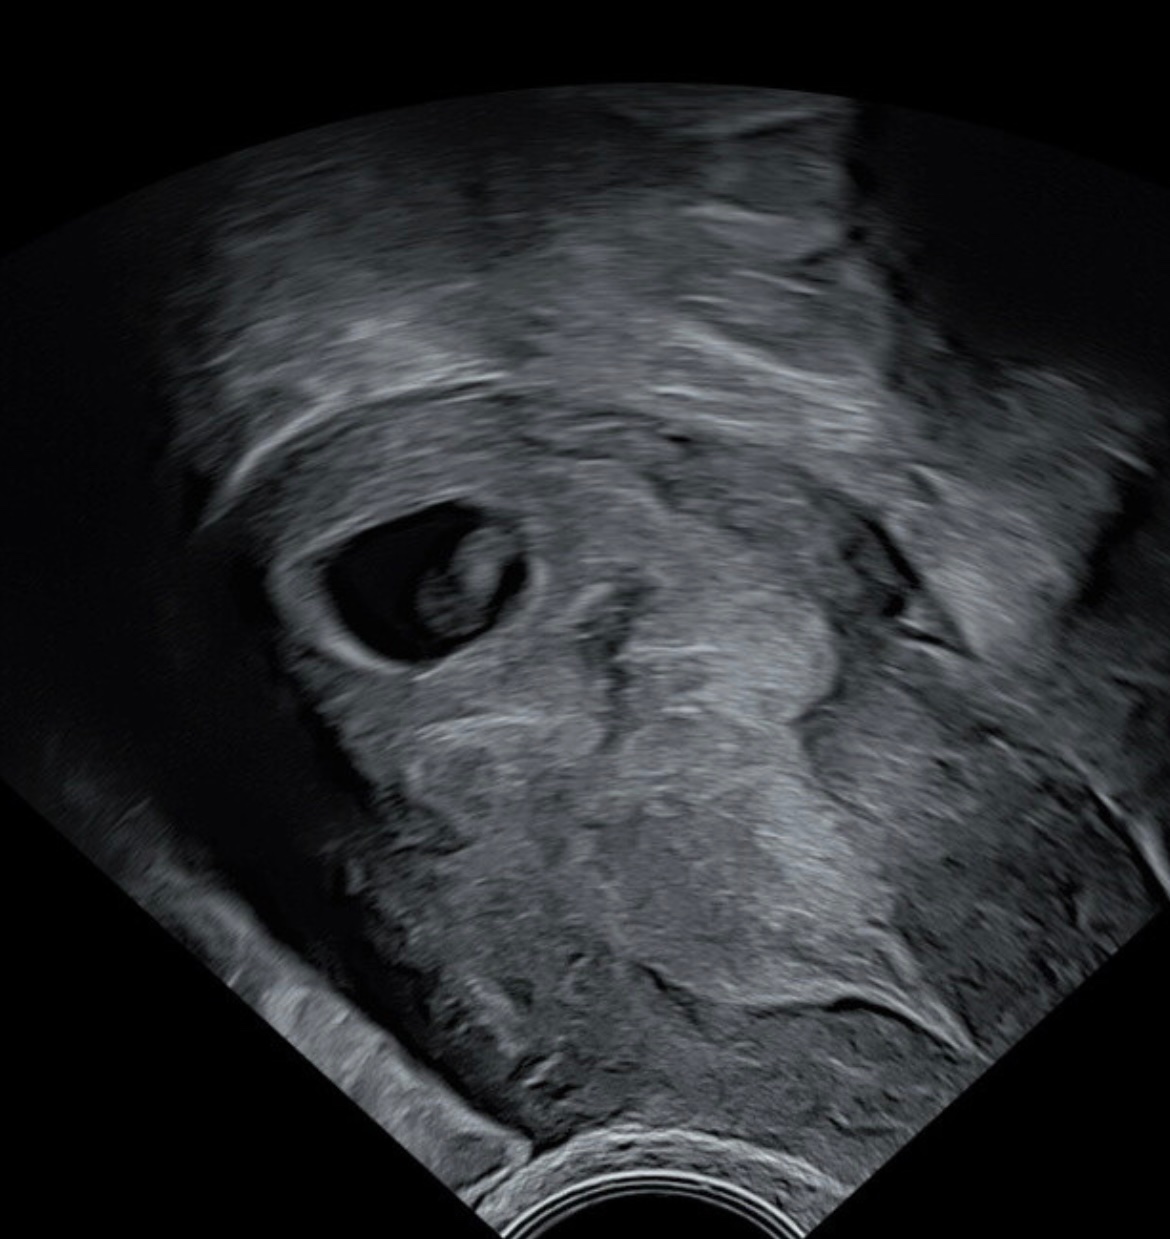

Bønna sitter litt høyt mot høyre, men legen på Spesialistsenteret for kvinner mente dette skulle gå helt fintMålte nøyaktig 6+2 og hjerteslag på 120